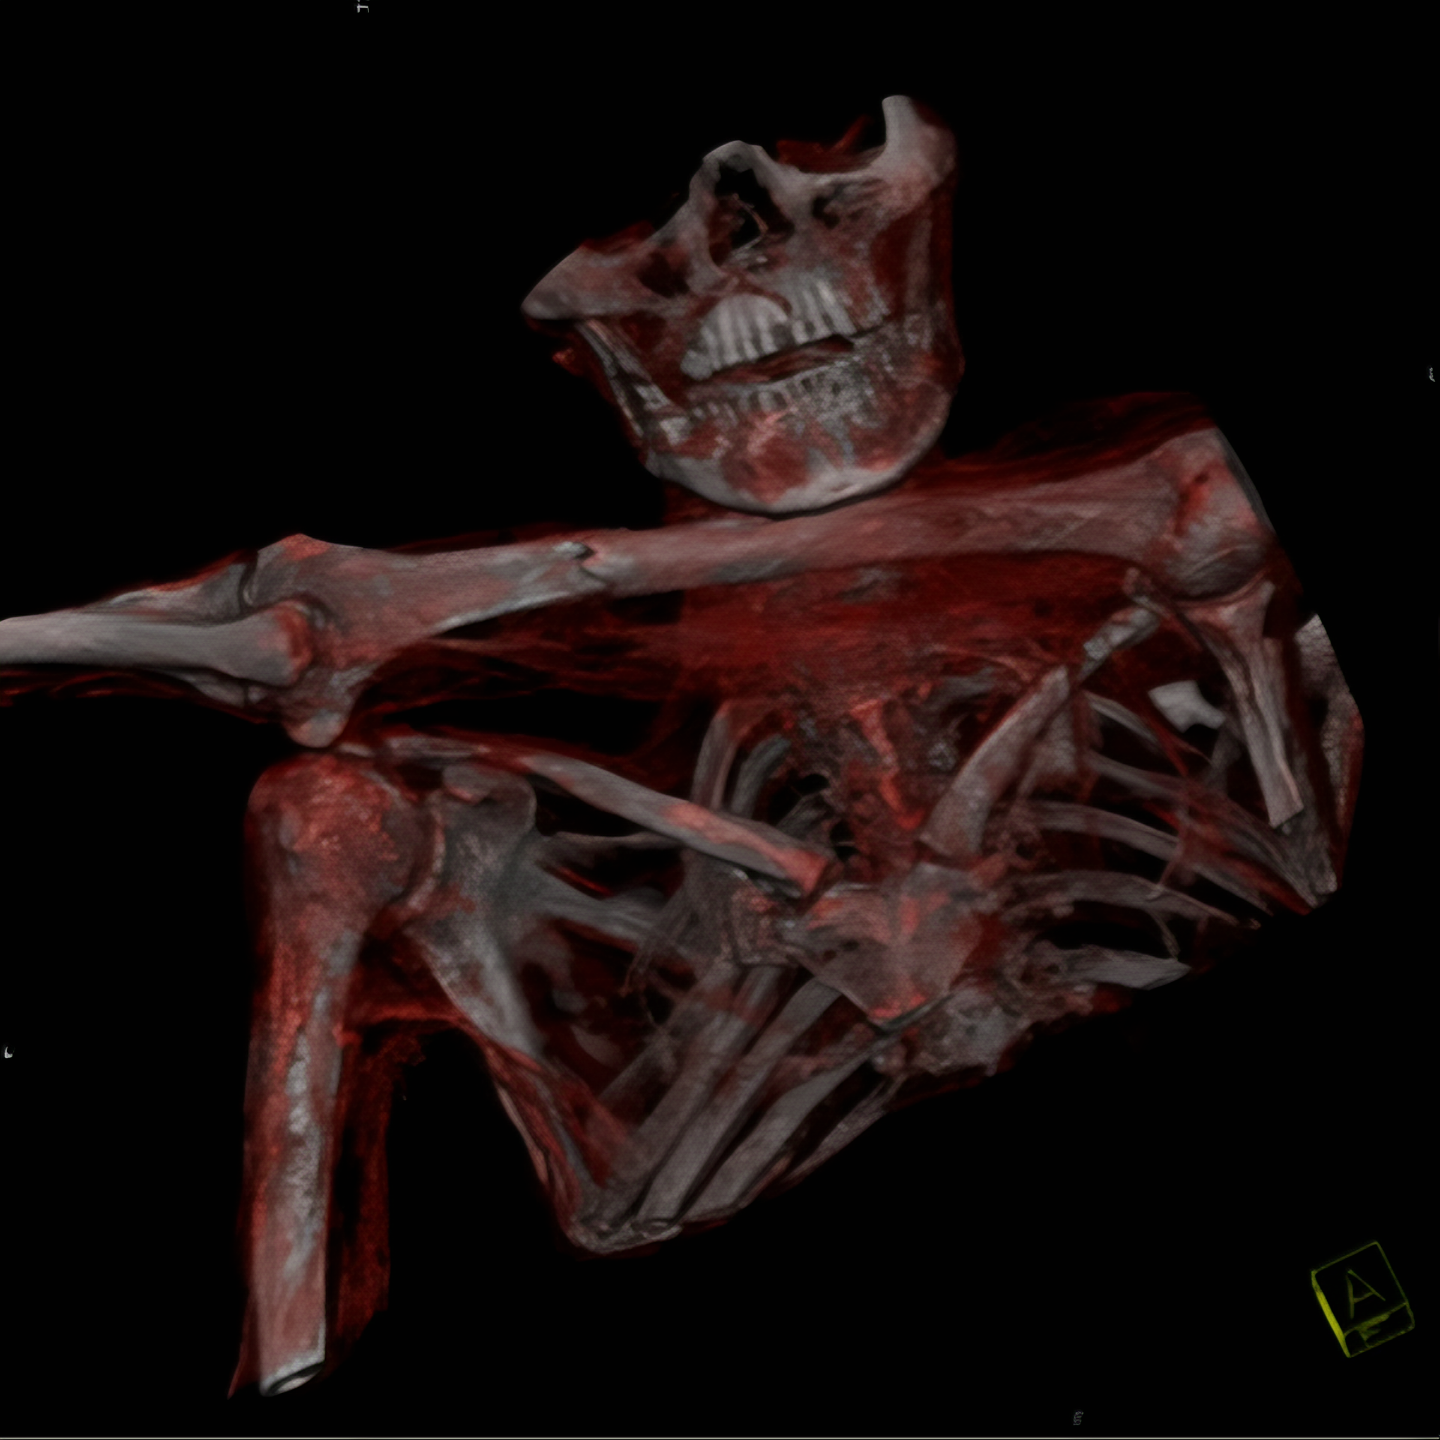

외치에 대한 CT 검사에서는 수상 한 부분이 더 두드러졌다.

그의 왼쪽 견갑골 부분에서 2 센티 정도 폭의 구멍이 발견된 것.

이 구멍은 그의 왼쪽 폐 언저리까지 뻗어 있었다.

우선 외치에 대한 신체검사가 재개되었는데 이 과정에서 병리학자인 Eduard Egarter Vigl은 외치 어깨 부분 피부에서 매우 수상한 피부 손상을 발견했다.

CT로 찾은 외치 어깨 부분 구멍은 이 피부 손상 부분에서 시작된 것은 분명해 보였다.

이 피부를 뚫고 들어간 무엇인가가 외치 영감님 몸 안으로 파고 들어간 것이다.

이 조사에서 확인 된 것은, 외치의 몸안에 남아 있는 것은 돌로 만든 화살촉.

아마도 그는 죽기 전 누군가가 쏜 화살에 맞았을 터인데 그 뚫고 들어간 양상을 보면 왼쪽어깨 빗장밑동맥 (subclavian artery)을 건드렸을 것이다.